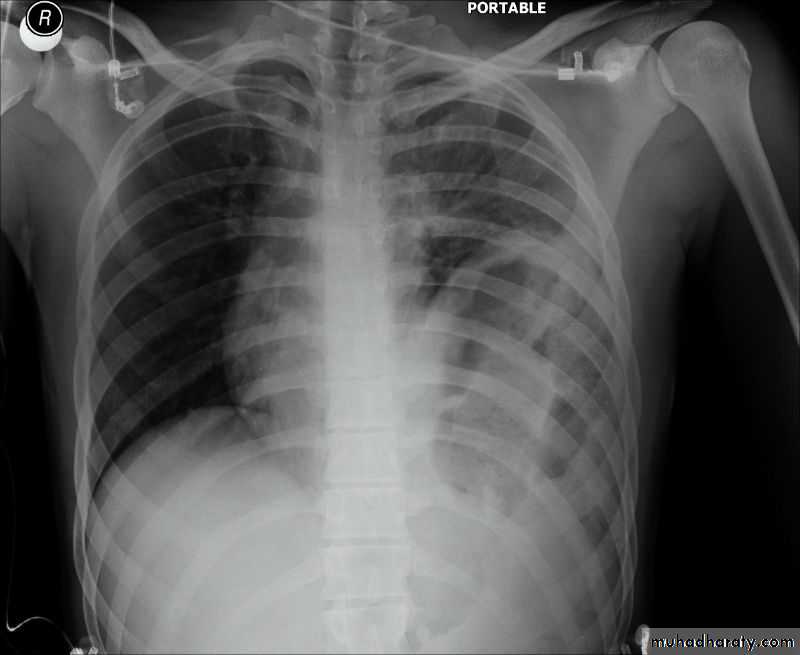

History: dyspnea, weight loss, dehydration with poor immunity

History; too shy to take of his shirt in the pool!